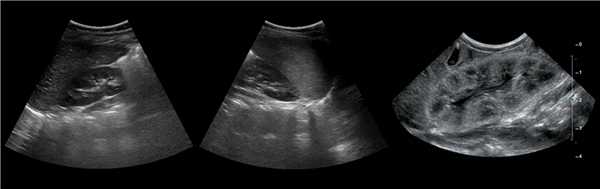

Клинический пример из первой группы. Пациент М., с хронической почечной недостаточностью. Трансплантация почки произведена от живого родственного донора. Трансплантат находится в правой подвздошной области. При нормальном функциональном состоянии трансплантата, показатели цветовой и спектральной допплерографии оценивались как удовлетворительные, с индексом резистентности не более 0,60 (рис. 1); показатели жесткости паренхимы почечного трансплантата при УЭСВ на различных участках составили от 20,05 до 29,18 кПа (рис. 2-4).

Рисунок 2. Исследование в режиме ультразвуковой эластографии сдвиговой волны у пациента М.: жесткость паренхимы в зоне медиального края трансплантата 19,8 кПа

Рисунок 3. Исследование в режиме ультразвуковой эластографии сдвиговой волны у пациента М.: жесткость паренхимы в зоне верхнего полюса почечного трансплантата 21,4 кПа

Рисунок 4. Исследование в режиме ультразвуковой эластографии сдвиговой волны у пациента М.: жесткость паренхимы в зоне нижнего полюса почечного трансплантата 16,8 кПа

У пациентов второй группы, при нормальных показателях клинико-лабораторных и допплерографических исследований, показатели жесткости почечного трансплантата составили 17,00-26,06 кПа.